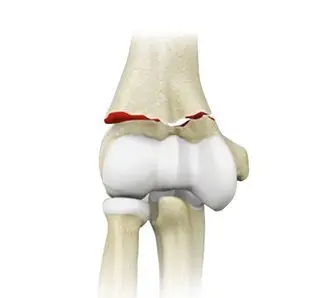

Patella Fracture

Elbow Fractures